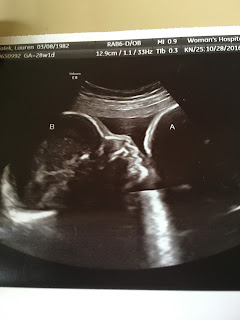

Twenty-eight weeks pregnant with Joseph and Caroline here.

This is an ultrasound picture from Mommy's 28 week doctor's appointment.  It looked as if baby girl kept "kissing" or "whispering" into baby boy's ear. I can't wait to kiss their cheeks and hold them in my arms!